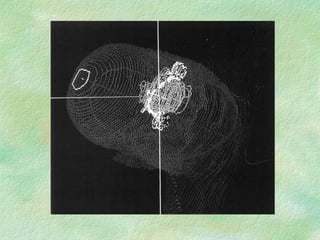

Virtual Simulation: -  Immobilization CT Coordinate system Structure Delineation Isocentre localization Beam placement/definition